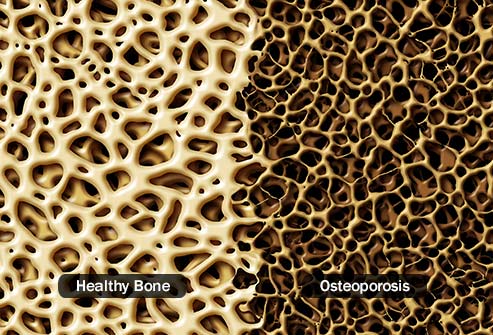

The cause of Alzheimer disease is unknown. Scientists know that in Alzheimer disease there is large build-up of proteins called amyloid within brain cells. These proteins occur normally, but not yet understand why they build up in large amounts. The disease process can go on for many years without symptoms, but as more and more proteins form brain cells,the cells lose their ability to function and eventually die. This causes the affected parts of the brain to shrink.